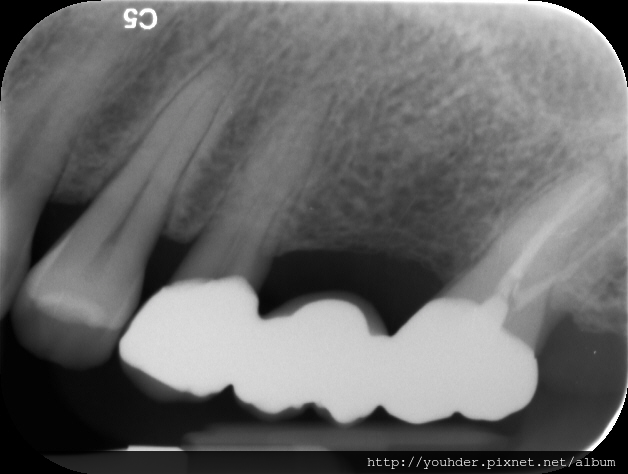

患者A先生

上顎 正面 下顎

患者B小姐

以上兩位患者口內狀況非常複雜,要制定一個好的治療計畫,

不只要考慮到患者的牙齒條件,

還要顧及患者意願、時間、金錢、評估可獲得的結果等等。

所以像這類型的Case 醫師通常在初步的溝通後會先做出一兩個不同的治療計畫,

再和患者解釋,了解患者接受程度。